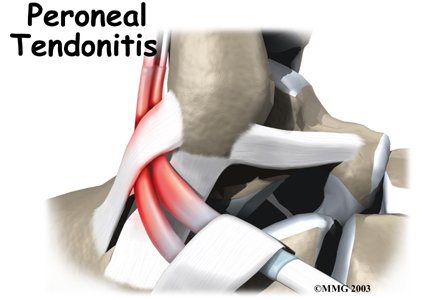

Peroneal tendon problems mostly occur where the tendons glide within the pulley behind the lateral malleolus. Their movement can cause irritation of the lining of the tendons. This condition is called . The irritation can also occur after an ankle injury, such as a blow to the outside of the ankle or an ankle sprain.

Peroneal tendon problems mostly occur where the tendons glide within the pulley behind the lateral malleolus. Their movement can cause irritation of the lining of the tendons. This condition is called . The irritation can also occur after an ankle injury, such as a blow to the outside of the ankle or an ankle sprain.

Repetitive ankle motions in sports, such as running and jumping, can lead to wear and tear on the tendons inside the groove. A high arch puts extra tension on the peroneal tendons within the groove and has also been found to cause peroneal tendon problems.

Peroneal tendon problems commonly occur from an ankle sprain. During the typical inversion ankle sprain, the foot rolls in. This type of injury sprains or tears the ligaments that support the lateral part of the ankle. The forceful stretch on the peroneals when the foot rolls in can also cause a lengthwise tear in the peroneal tendons.

Patients with peroneal tendon problems usually describe pain in the of the ankle or just behind the lateral malleolus. This pain commonly worsens with activity and eases with rest. Patients may have swelling behind or under the lateral malleolus. They may notice more pain when pressure is applied along the tendons.